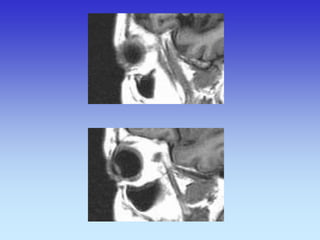

ORBITE

PRIJELOM DNA ORBITE

KORONARNI SLOJ

CT ORBITA